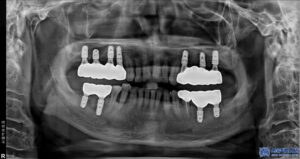

발치를 진행한 후, 우선적으로 하악 좌우 어금니

부위부터 무절개 임플란트를 총 4개 심었습니다.

이 과정에서는 뼈 이식도 병행하였습니다.

상악 좌우는 모두 뼈이식을 동반한

무절개임플란트를 총 6개 식립하였습니다.

이처럼 총 10개의 무절개 임플란트를

식립하게 되었는데요.

미리 3D CT를 통해 정밀한 위치를 컴퓨터로 분석하고,

고성능 3D프린터로 만든 “수술 가이드”를 이용해

임플란트를 심기 때문에 출혈과

통증이 적고 회복도 빠릅니다.

무절개 방식은 특히 임플란트의 “식립 각도”를

정밀히 맞추는 데 큰 도움이 됩니다.

이는 임플란트 성공률에 직결되는 요소로,